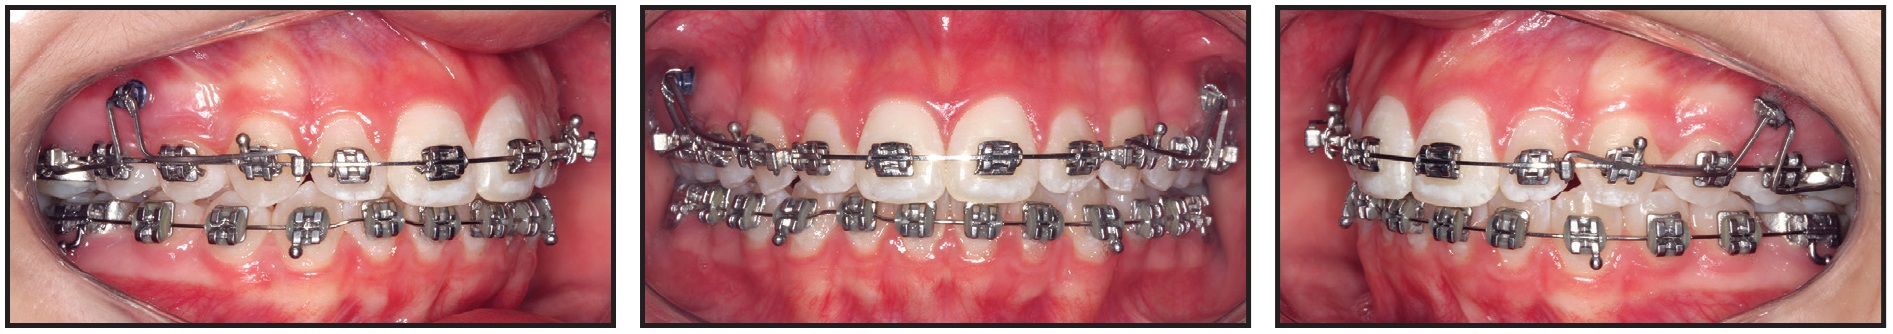

After seven months of treatment, the initial alignment was complete. A bracket-head mini-implant (1.5mm × 8mm, with a 1mm transmucosal collar) was inserted on each side between the upper premolars to provide skeletal anchorage for the DAVIT device (Fig. 7). The right and left mini-implants had counterclockwise and clockwise thread directions, respectively, to prevent screw failure due to the rotational force load.35 The posterior power arms of the DAVIT were activated above the .019" × .025" alignment archwire to produce a posterior intrusive force of about 300g per side. The anterior power arms were activated below the archwire to produce an anterior extrusive force of about 150g on each side, for a total 300g of anterior extrusive force. The horizontal anchorage segments of the DAVIT were tied into the mini-implant bracket slots with .008" stainless steel ligature wire. Finally, the activated vertical plugs at the ends of the horizontal power arms were inserted into the vertical slots of orthodontic cross-tubes positioned between the lateral incisor and canine and between the second premolar and first molar on each side of the maxillary arch.

Fig. 7 After seven months of alignment, mini-implants inserted between upper premolars, and DAVIT appliances activated to correct open bite by posterior intrusion and anterior extrusion.

After two months of treatment with the DAVIT appliance, the open bite was completely closed and interocclusal contact between the premolars had substantially increased (Fig. 8).

Fig. 8 After two months of DAVIT treatment, open bite closed and vertical relationship between premolars substantially improved.

To minimize the possibility of post-treatment relapse,38 however, the DAVIT was reactivated using the same protocol. Two months later, the desired overcorrection had been achieved (Fig. 9).

Fig. 9 After four months of DAVIT treatment, overcorrection of open bite obtained.